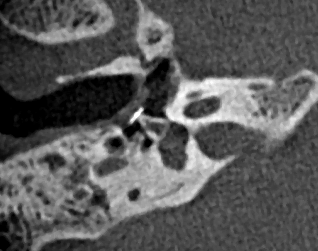

Ambossarrosion mit Stapesprothese Stapesprothese Teflon (Causse) PORP auf Stapes PORP Titan auf Stapes PORP PORP Titan disloziiert Otosklerose Otoskleroseherd TORP Pauke nicht belüftet TORP unter Knorpelinsel disl.